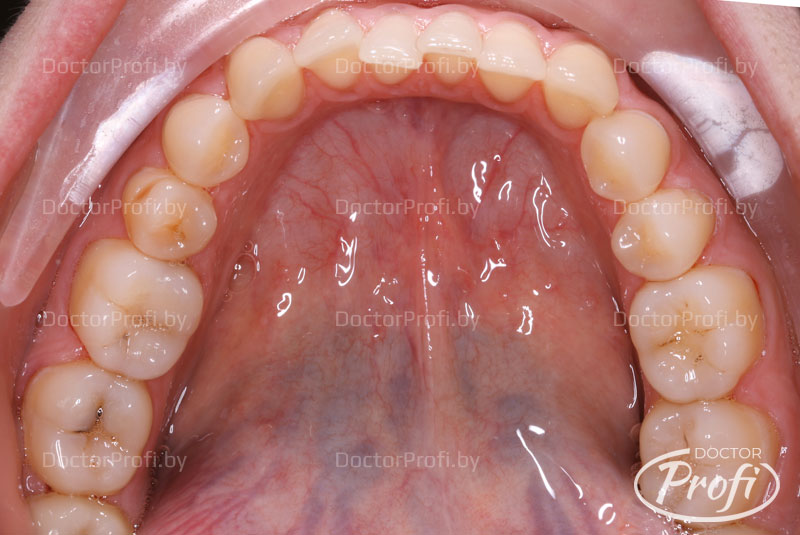

Пациентка обратилась в клинику с жалобами на неэстетичный зубной ряд. Возраст - 30 лет. На консультации у ортодонта были выявлены следующие проблемы с прикусом: двусторонний перекрестный прикус, открытый прикус в переднем отделе, сужение зубных дуг, скученное положение резцов верхней и нижней челюсти, относительная микродентия зубов 12, 22, инфантильный тип глотания.

Срок лечения составил 15 месяцев. В результате проведенного лечения пациентка обрела красивую улыбку, правильный прикус, ровные и здоровые зубы.